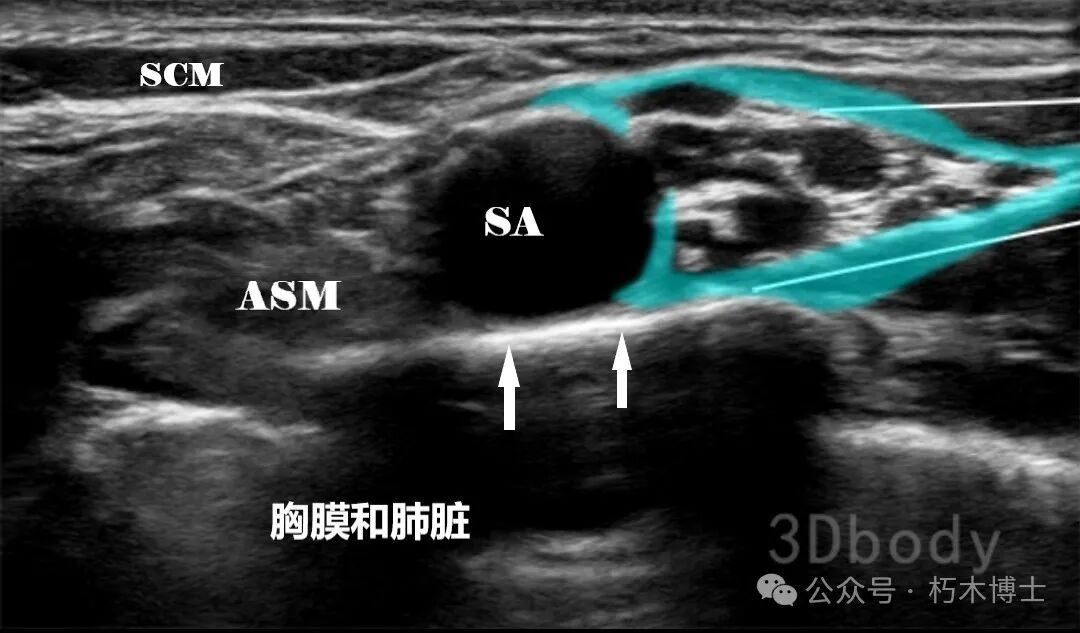

![]()

图2. SCM:胸锁乳突肌;ASM:前斜角肌;SA:锁骨下动脉。白色箭头处为第一肋,黑色葡萄状结构为臂丛。浅蓝色为注射区域,白色直线为注射针。(图源:3Dbody)

4. 操作要点: - 患者头转向对侧。 - 皮肤消毒,探头横向放置在锁骨中点上方,滑动显示锁骨下动脉。 - 向头侧或尾侧倾斜探头,获得清晰锁骨下动脉断层超声解剖图,动脉外侧方的一簇低回声椭圆形结构即臂丛。 - 平面内技术,从探头外侧进针,穿过椎前筋膜或臂丛鞘,回抽无血、空气,两点或三点注射局麻药 20-25ml。**三、锁骨下入路** - 喙突旁(经典入路) 1. 超声解剖图:在胸大肌和胸小肌深面可见腋动脉,腋动脉周围是臂丛的三个束,腋静脉位于腋动脉深部或表层。